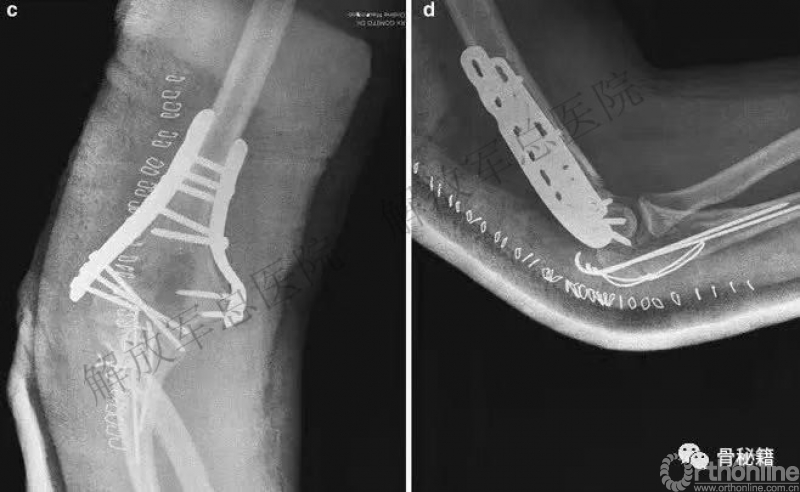

肱骨远端骨折的固定若没有熟练掌握,极易产生一些并发症。最常出现的并发症:僵硬、骨不连、感染、尺神经、内固定相关。

看看这些失败的case,肱骨远端不简单!